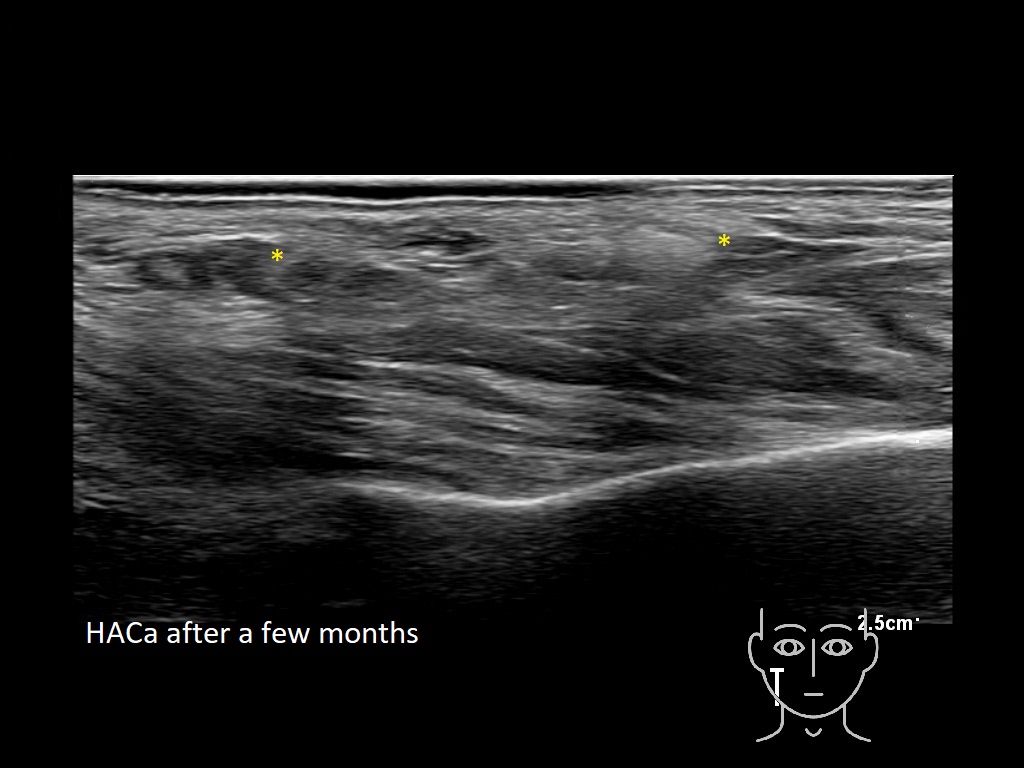

Draw in the second image below where the fillers are located. To check if your answer is correct, swipe the first image to the right.

HAca 1b e